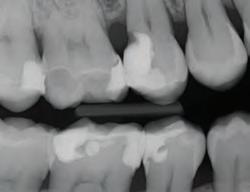

DISTO-OCCLUSAL CLINICAL CASE